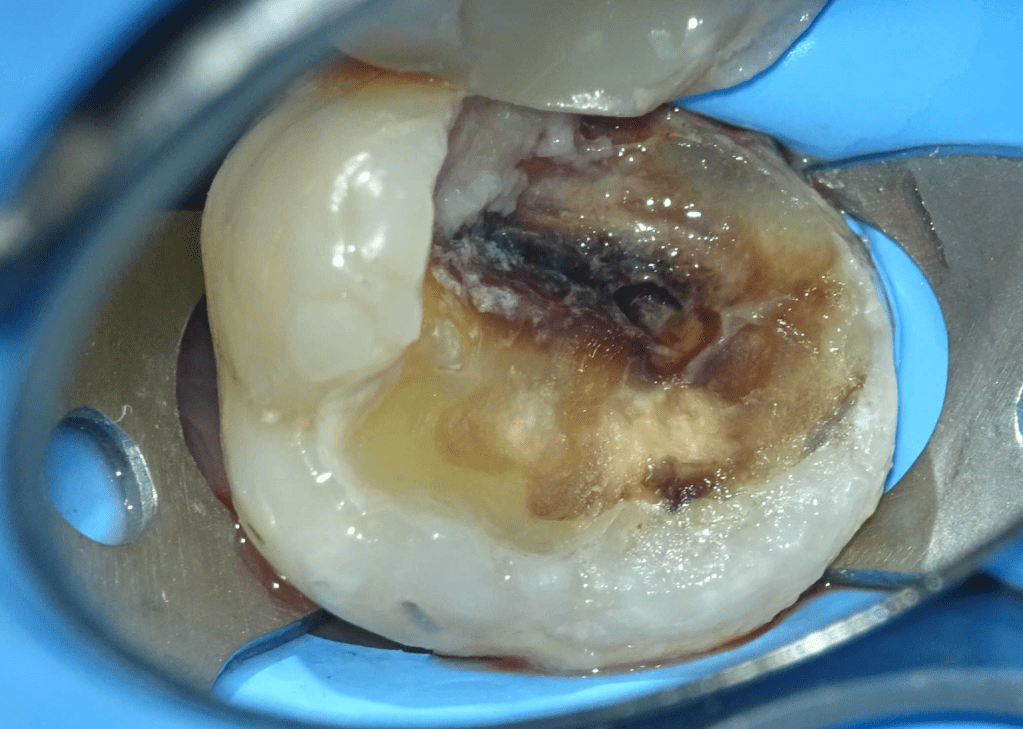

Pulpotomía biodentine + reco preendio